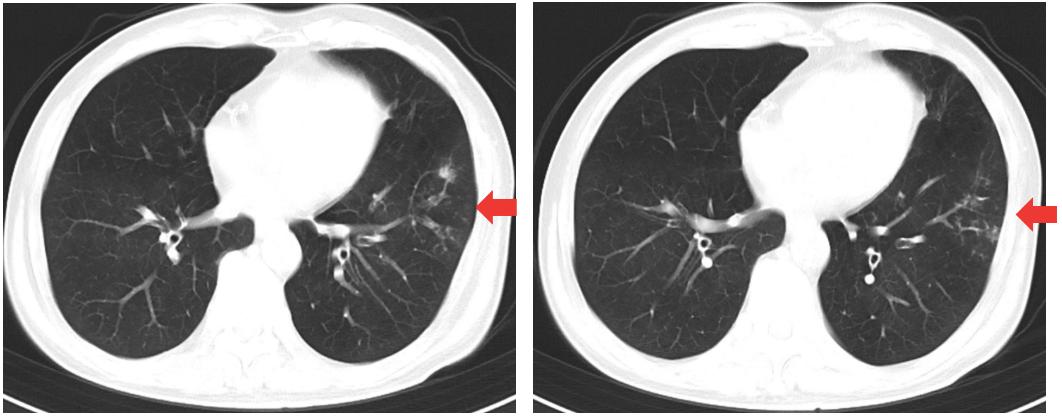

20220110肠镜检查:插镜至回末,距肛缘28~10cm可见四壁黏膜鹅卵石样表现、散在溃疡、小片状糜烂、可见新鲜血迹及脓性分泌物,10cm至肛缘四壁黏膜散在红斑、充血水肿明显(图1)。诊断为UC、E2、活动期、乙状结肠Mayo 3分、直肠Mayo 2分。

图1 入院时肠镜检查图

20220704 肠镜检查(图7):提示粘膜愈合

图7 2022年7月4日肠镜复查